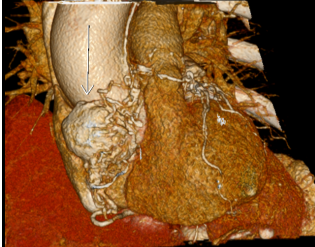

在心房重建时

发现心脏上长了一个

很大的瘤子!

这个结果

让医生和患者都十分震惊

双侧颈动脉体及心脏

为神经内分泌肿瘤

答案明确了!

余淑华告诉王阿姨

她的心脏肿瘤

和双侧颈动脉体瘤

考虑为副神经节瘤

需要外科手术切除肿瘤